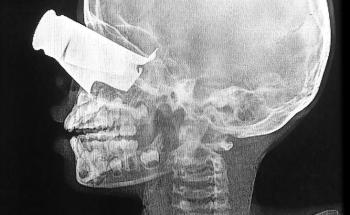

The situation there is ‘horrific’ and ‘catastrophic’. Hospitals and clinics – the ones that are running – are overwhelmed and are barely functioning, running out of electricity and medical supplies. Surgeons in Al-Shifa hospital are now operating without painkillers. As a surgeon myself, this is unimaginable.

There are very little medical supplies. Surgeons in Al-Shifa Hospital have been operating without anaesthetics or painkillers. Contact with our staff is sporadic; we frequently lose contact with them. We have not been able to contact our staff in Al-Shifa Hospital since 16 November.